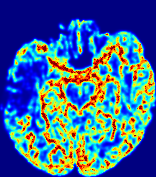

Figure 5: Predicted concentration time series for the same patient shown in Fig. 3, where (i)-(vi) correspond to slices #1-6 respectively. Each grouped row displays (a) the measured concentration image sequences and (b) the predicted concentrations at corresponding time points.

3.2 Predicted CA Concentration

To better illustrate the prediction accuracy, and therefore the estimation accuracy of 𝐕𝐕{\bf V} and D𝐷{D}, of PIANO, we provide the corresponding predicted time-series of CA concentration images in Fig. 5 and Fig. 6 for the same patients in Fig. 3 and Fig. 4, respectively. We see that PIANO is capable of predicting the CA concentration given their initial state, indicating its ability to successfully capture 𝐕𝐕{\bf V} and D𝐷{D}. Note that although the concentration values for these two patients differ considerably, caused by the different total volume of injected CA, PIANO is still able to provide plausible estimates.